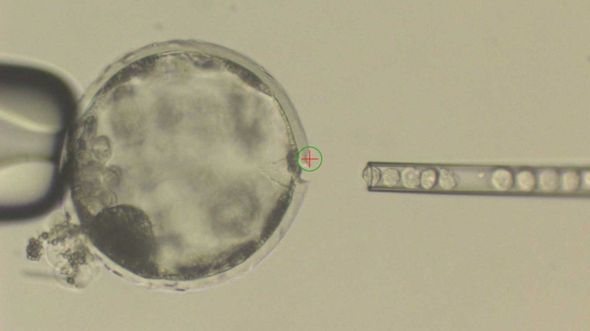

| Tế bào người được cấy vào phôi lợn. Ảnh: BBC |

Theo dự án này, các tế bào của người được cấy vào phôi thời kỳ đầu thai kỳ của lợn. Trong số 2075 phôi thai được cấy ghép, chỉ có 186 phôi tạo thành ‘quái vật’ chimera. (Chimera là tên một loài quái vật người nửa sư tử, nửa dê trong thần thoại Hy Lạp).

Theo BBC, trong cơ thể của chimera chỉ có 0,001% tỷ lệ là từ người, còn lại là từ lợn.

Lợn bình thường mang thai 112 ngày, nhưng các phôi chimera chỉ được nuôi dưỡng trong 28 ngày, sau đó được đưa ra ngoài để nghiên cứu.

| Phôi chimera - lợn mang tế bào người. Ảnh: BBC |